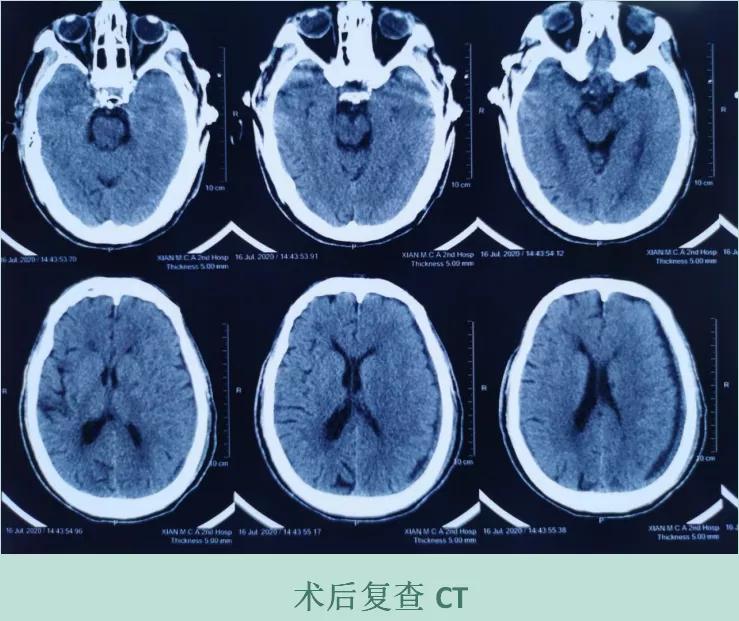

手术圆满成功后,张大爷肢体肌力恢复,复查CT见血肿清除,脑组织膨胀良好。现恢复良好,可适当下地活动锻炼。张大爷和家属对治疗效果都特别满意。